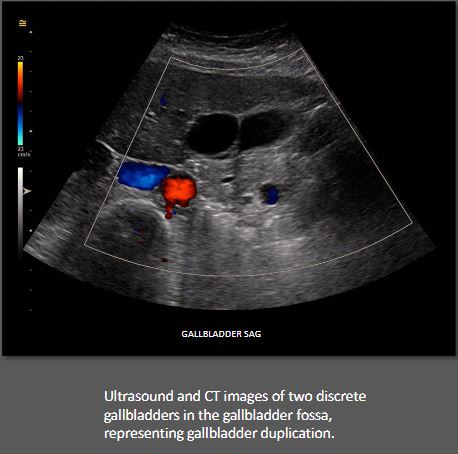

The gallbladder is one of the most frequent organs in our body subjected to anatomical variations. These variations may involve the organ's number, shape, and location. Duplication of the gallbladder is a congenital number variant. It has been described in animals and humans since ancient times. For example, the Talmud, the book of ancient Jewish "teachings," has a reference to the dietary laws stating that the presence of a duplicated gallbladder rendered an animal unsuitable for eating. The first reported case of gallbladder duplication in humans was reported in a sacrificial victim of Emperor Augustus in 31 BC. At the beginning of the 20th-century American anatomist, Boyden examined I0,000 domestic animals and found congenital gallbladder duplications in 1 of 8 cats, 1 of 28 calves, and 1 of 85 lambs and sheep. However, he encountered only 5 cases of this anomaly in more than 19000 human cadavers. The first documented case in a living human was recorded in 1911 after a double cholecystectomy was performed for a duplicated gallbladder. Since then, scattered case reports of this rare congenital anomaly accumulated over the years. It is now understood that gallbladder duplication has an approximate incidence of 1 in 3800-5000 births. However, the precise incidence of this rare malformation cannot be accurately assessed since the only cases that can be identified are those that became symptomatic or were encountered as incidental findings during imaging studies, surgery, or at autopsy. GALLBLADDER SAG122

n ultrasound, duplicated gallbladder presents as two discrete adjacent gallbladder lobes as opposed to a single oblong vesicle. Sonographic evaluation of the gallbladder is considered the most helpful and highly sensitive diagnostic tool in assessing gallstones, cholecystitis, and other gallbladder conditions. However, in the setting of the duplicated gallbladder, ultrasonography may not completely differentiate it from other conditions such as Phrygian cap or choledochal cyst. Also, differentiation of the specific type of duplication is typically not possible with ultrasound alone since even with current real-time equipment, the cystic duct is challenging to identify. CT and MRI are more effective imaging techniques to confirm the diagnosis and delineate the classification type of suspected gallbladder duplication